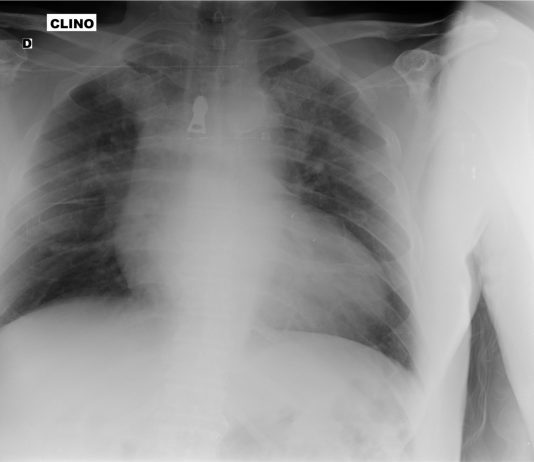

Maschio, 50 anni, non co-patologie, sintomatico da due giorni, in peggioramento, con tosse secca, piressia oltre 38°C, astenia. Si rileva saturazione pO2 93 % in aria ambiente.

PERCORSO CLINICO DIAGNOSTICO: il paziente giunge in...